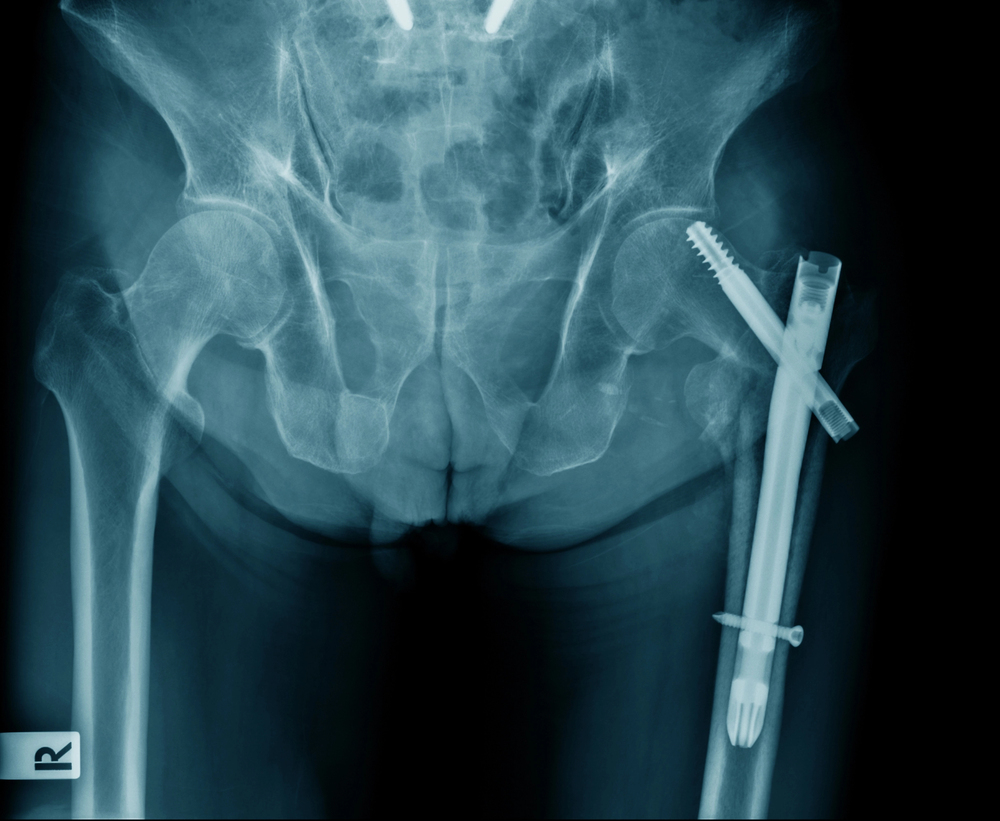

Common surgical procedures for broken femurs include Open Reduction Internal Fixation (ORIF) surgery and hip replacement surgery.

Open Reduction Internal Fixation involves realigning the broken thighbone and securing it with plates and screws. In contrast, hip replacement surgery involves replacing the damaged hip joint (which often happens together with a femoral shaft fracture) with an artificial joint.